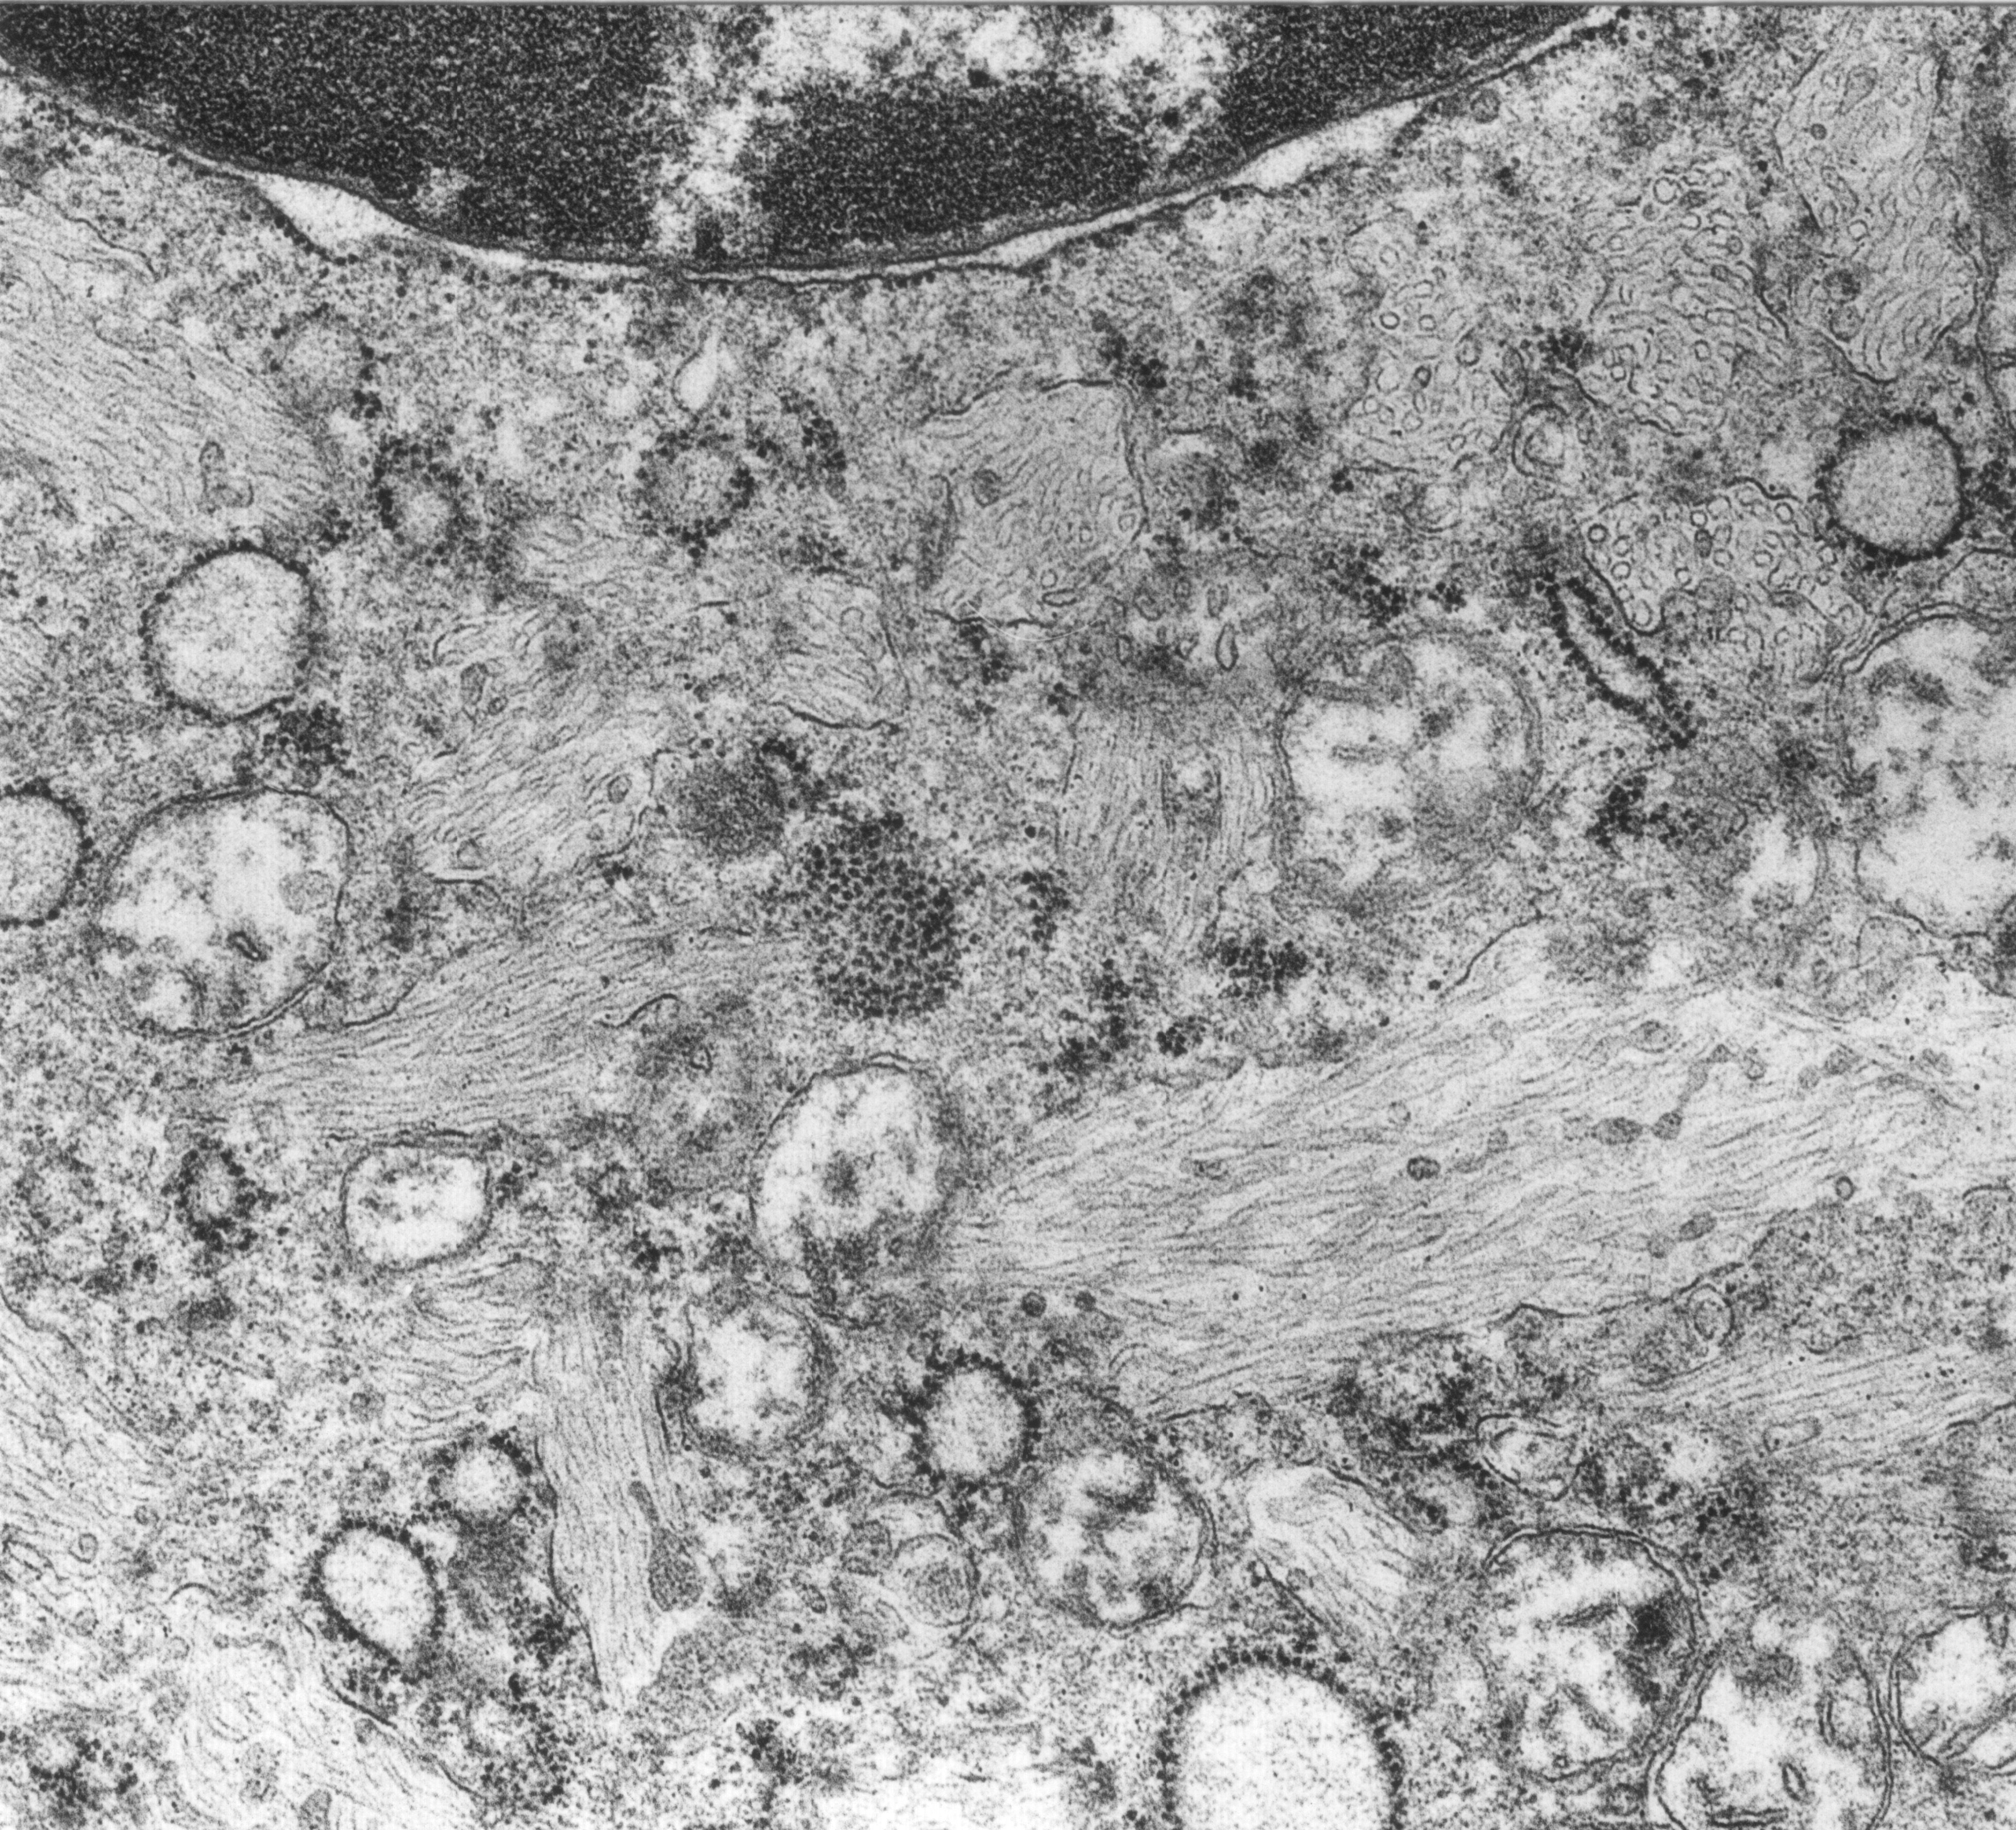

Morbus Gaucher ist eine seltene, erbliche Fettspeicherkrankheit. Weltweit erkrankt durchschnittlich 1 von 40.000 Menschen. Bei der am häufigsten vorkommenden Variante erfolgt die Erstdiagnose meistens im Alter von 20 bis 30 Jahren. Die Erkrankung betrifft Frauen und Männer gleichermaßen. Bisher war bekannt, dass die Erkrankung ursächlich nur durch den genetisch bedingten Mangel eines bestimmten Enzyms (ß-Glukozerebrosidase) verursacht wird. Durch den Enzymmangel werden zuckerhaltige Fettstoffe nicht korrekt aufgespalten und abgebaut. In der Folge reichern sich diese so genannten Glukosylceramide in verschiedenen Immunzellen an, vorzugsweise in den Fresszellen (Makrophagen). Die geschwollenen Zellen, sogenannte Gaucher-Zellen, finden sich in großer Zahl in Lunge, Milz, Leber und Knochenmark. Dort setzen sie große Mengen entzündlicher Substanzen frei und führen in der Folge zur Gaucher-Erkrankung. Dabei kommt es je nach Schweregrad zu entzündlichen Funktionsstörungen innerer Organe und des Skeletts.